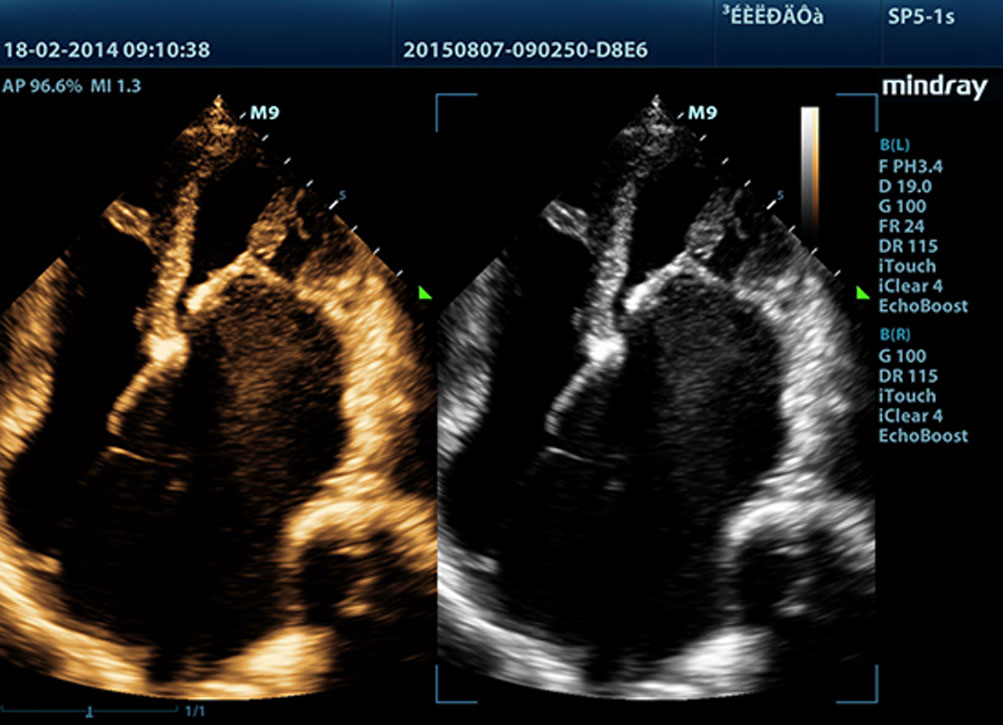

Echo Boost?

MindrayŌĆÖs unieke adaptieve signaalverwerkingstechnologie met intelligente echodetectie gebruikt ruwe signaal-ruis informatie om zwakke echosignalen te verbeteren en onderdrukt omgevingsruis. Dit resulteert in evenwichtigere helderheid en een verbeterde visualisatie van myocardiumweefsellagen.